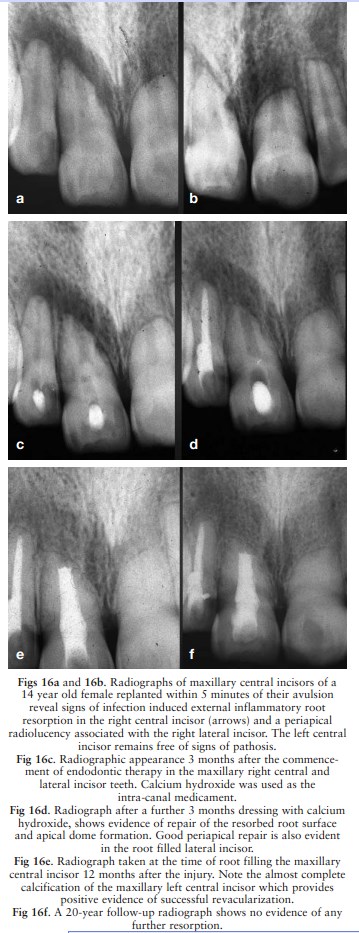

Calcium hydroxide has been widely used in the treat-ment

of external inflammatory root resorption

as illustrated in a case of external inflammatory root